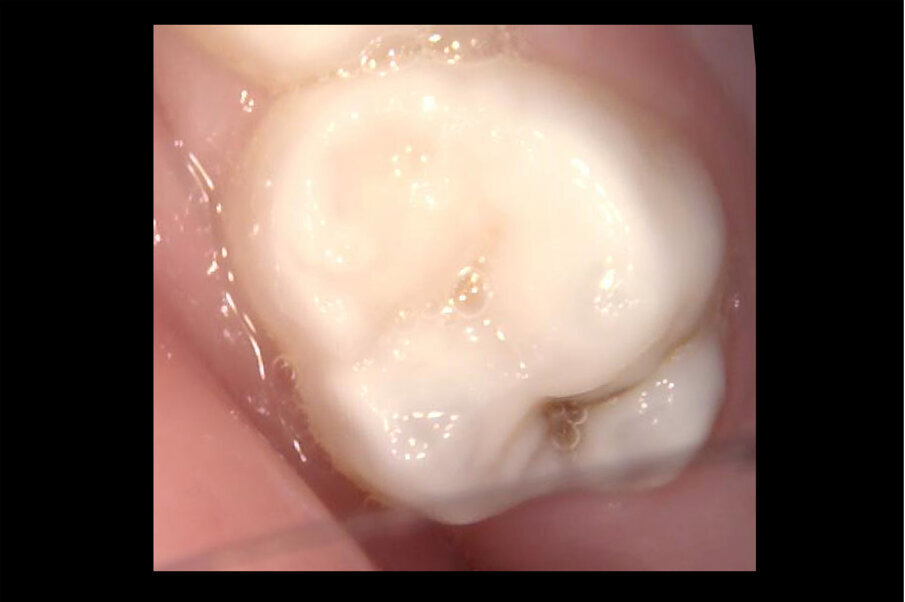

Afbeelding 7. Casus 3: 13-02-19. Intraorale foto 55 bij 3-jarig kind met zuigflescariës.

Afbeelding 8. Casus 3: 13-02-19. Intraorale foto 65 bij 3-jarig kind met zuigflescariës.